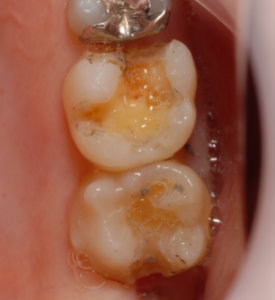

症例2

治療前です。

茶色の虫歯が見えます。

齲蝕検知液で染め出します。

赤く染まった部分が虫歯です。

完全に取り除きました。